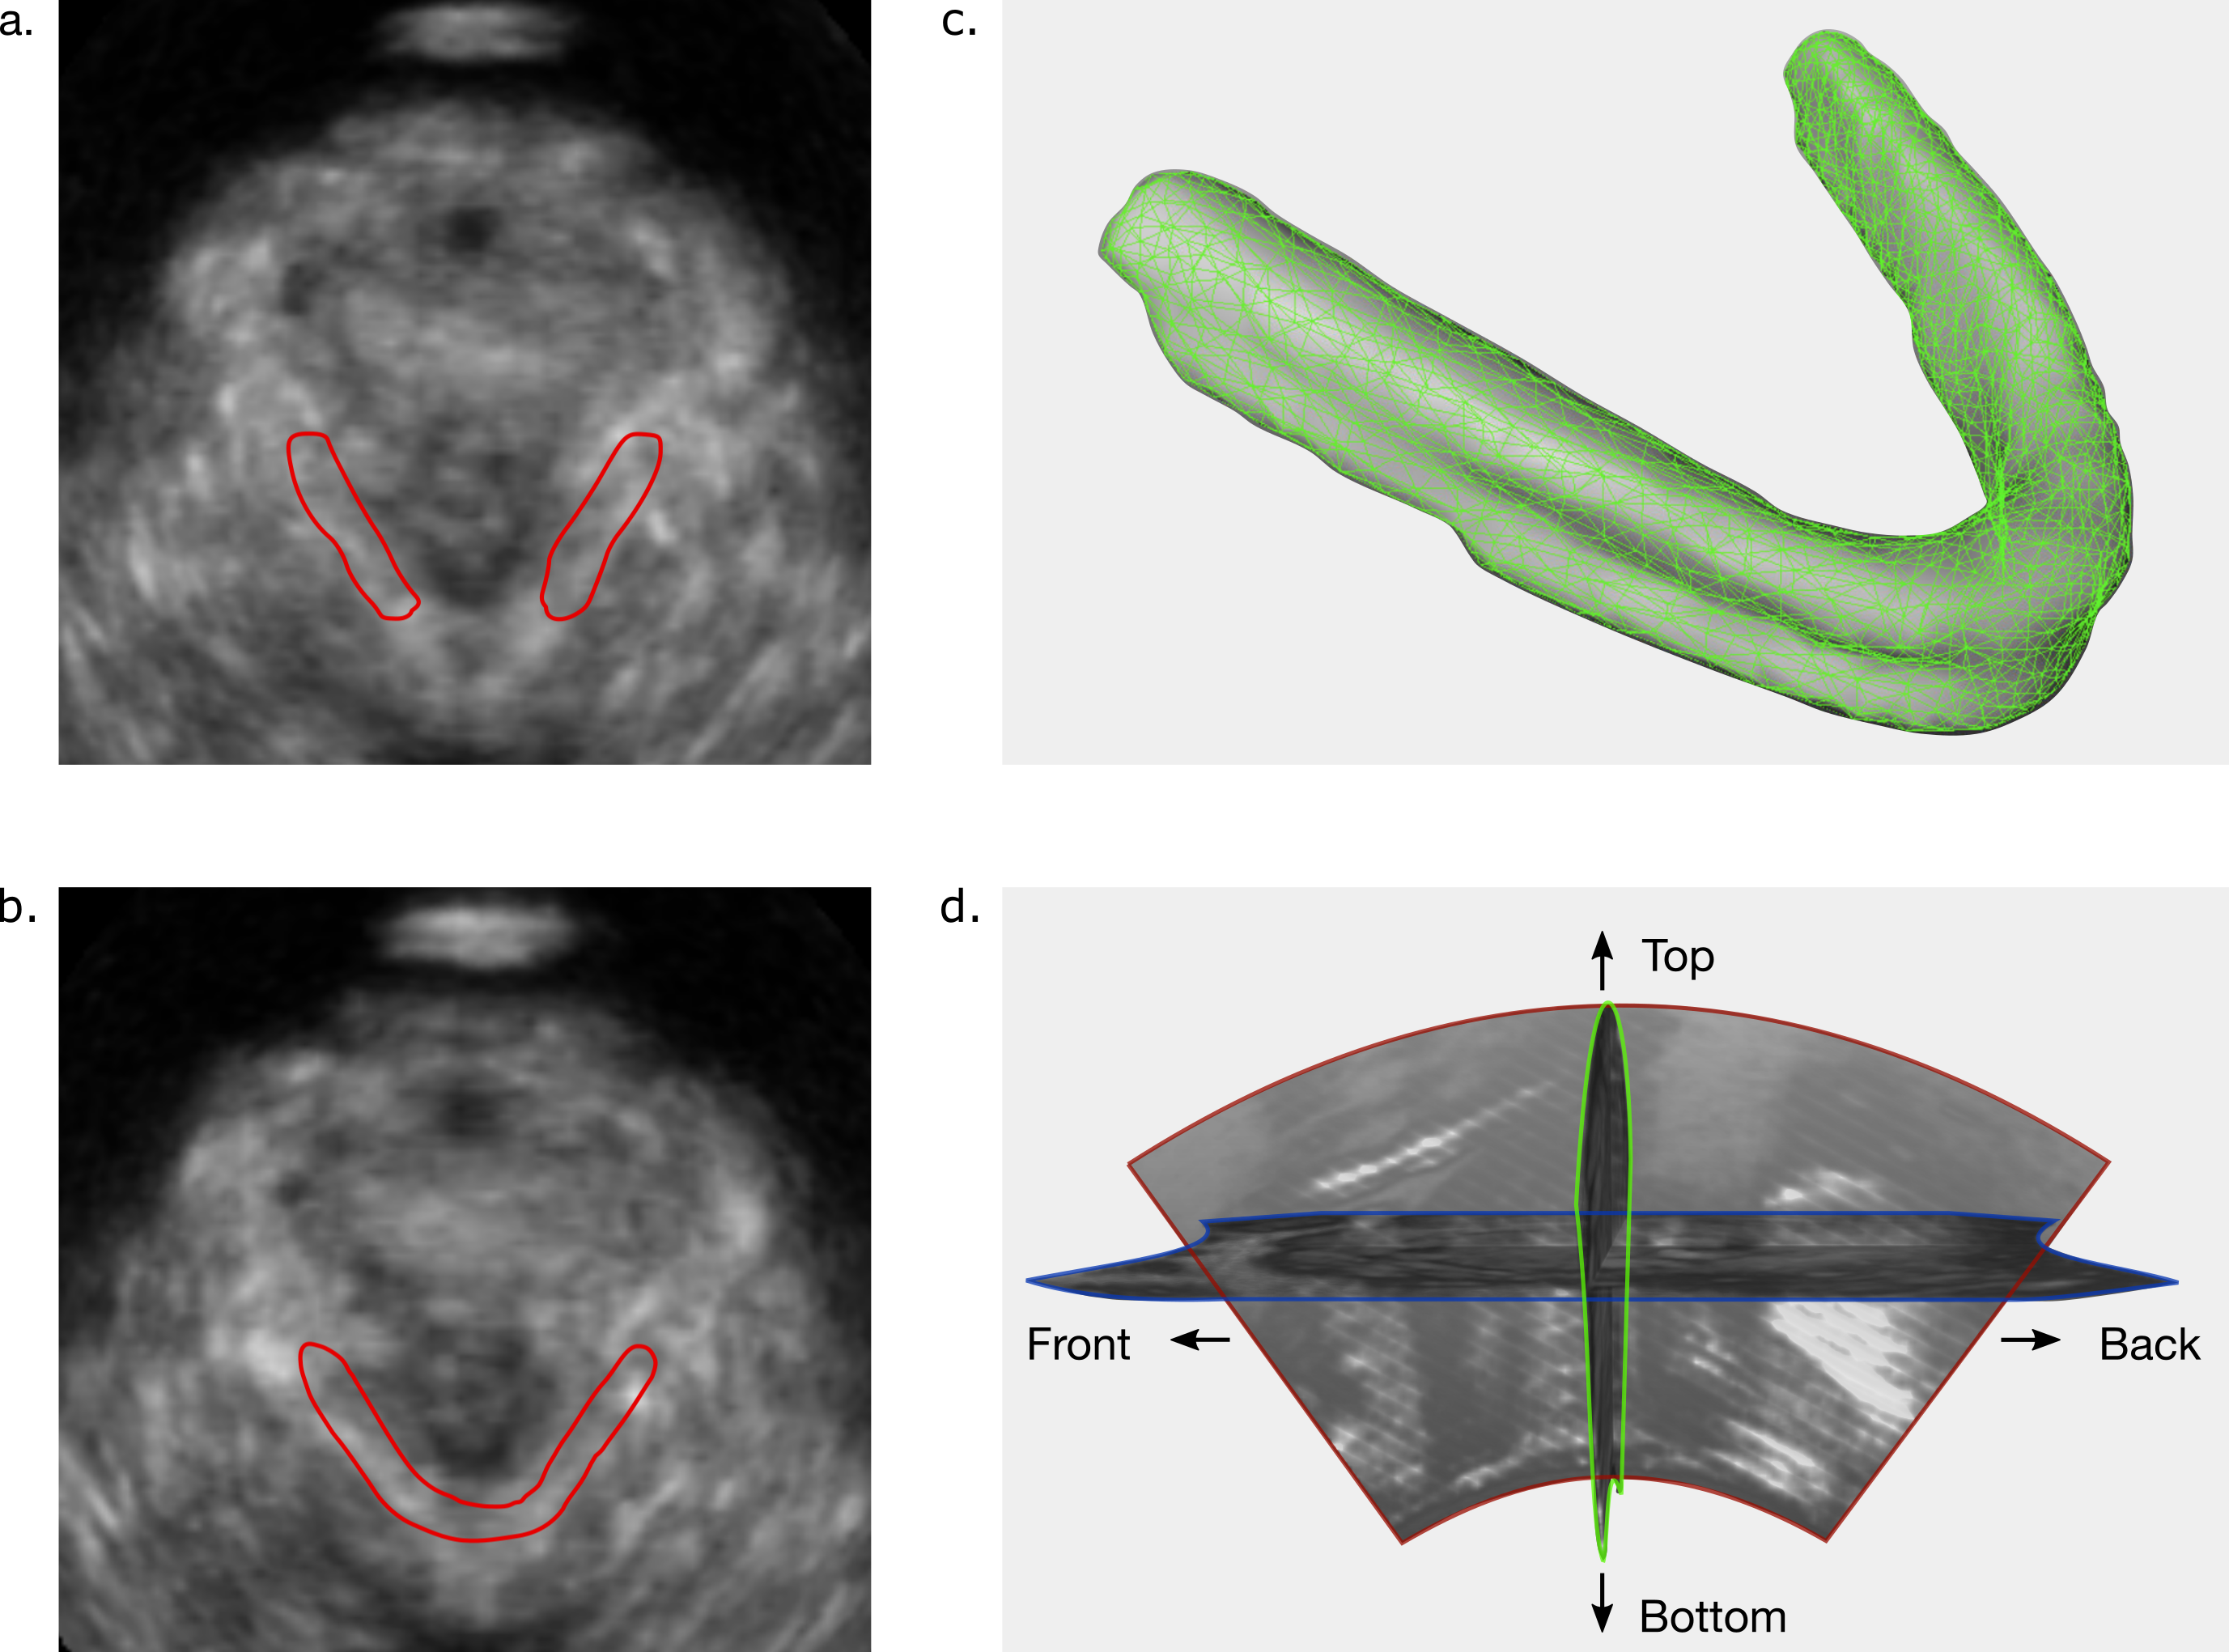

Figure 1: a. and b. show examples of axial slices looking similar but requiring different segmentation (red) based on 3D information obtained for the sagital and coronal view, highlighting the necessity of 3D contextual information for the segmentation of TPUS data. c. shows an example of a segmented LAM volume. d. visualizes three orthogonal slices form the ultrasound volume (green: coronal, blue: axial, red: sagital) and their orientation in the body. This examplifies the curved apex shape of the TPUS data.

3D segmentation of TPUS is a challenging task due to the noisy appearance of the data. The boundaries of the LAM are hard to distinguish due to the noisy appearance of ultrasound. Manual segmentation of this data is already challenging and requires the possibility to rotate the volume to slices that are not in one of the three standard planes and single slice segmentation requires anatomical references from the other views [9]. To exemplify this, we provide two axial slices (Figure 1 a. and b.) which look similar, but have different segmentations due to information from the coronal and sagital view. Therefore, we should incorporate large context information in our network design. Furthermore, we should have a deep network design: Low-level features are important for correct segmentation, since high-level features, such as local intensity differences, are not reliable due to the noisy boundaries.

Figure 1 c. shows the volume of a complete 3D muscle segmentation, from which can be observed that the LAM is a thin elongated structure (similar-to\sim1 cm in diameter and similar-to\sim12 cm long [7]). This makes segmentation of the LAM challenging for both manual and automatic segmentation, since a few voxels mismatch already can account for a relatively large volume shift. Furthermore, the class imbalance is large with only  0.5%percent\% of the voxels being muscle. The network training should be optimized to compensate for this. The automatic segmentation is considered successful if the segmentation accuracy is on par with manual segmentation accuracy between human observers [9].

We imported the data in MeVisLab (MeVis Medical Solutions, Bremen, Germany [44]) to manually segment the LAM on a single volume-frame at which the LAM was at rest (the movies captured muscle contraction and stretching as well). The data was further processed in Python after segmentation, the data size was made uniform by enlarging the volumes with zeros of a 256×\times256×\times154 volume, since this was a convenient volume size for axial training. We used a volume size of 256×\times256×\times128 for training with coronal and sagital slices. This results in a slightly cropped TPUS volume, however the ultrasound image shape is a curved apex so the top and bottom never contain muscle information (Figure 1 d.). The spatial resolution differs due to different depth settings during acquisition, voxels are cubic and \approx 0.5 mm along each dimension.